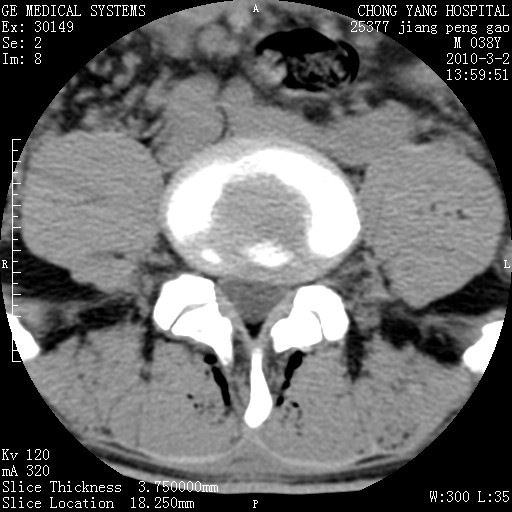

标题: CT24887:M38Y 反复腰痛 无外伤史 未做针灸 竖脊肌为何积气 [打印本页]

标题: CT24887:M38Y 反复腰痛 无外伤史 未做针灸 竖脊肌为何积气

退变,轻度增生/间盘膨出、l5椎后缘软骨结节。

肌间隙积气过多也为退变表现。

椎间盘突出,软组织积气。